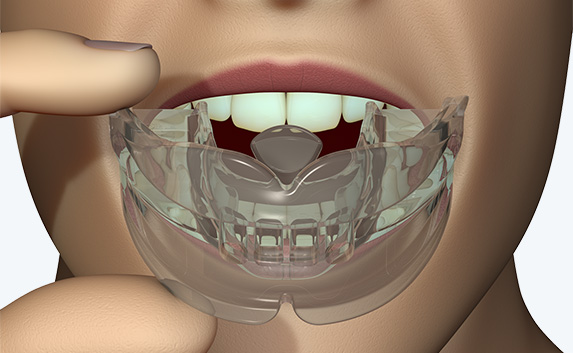

myobrace Medium Myobrace Orthodontic Teeth Trainer Appliance T1, Medium andの詳細情報

Myobrace Orthodontic Teeth Trainer Appliance T1, Medium and。S1。T3。子どもが使用しました。寝るときだけでも効果はあります。お試ししたい方へ。。T3。ポンちゃんです(他の方は購入出来ません)。SE11L ハンドピース OSADA オサダ